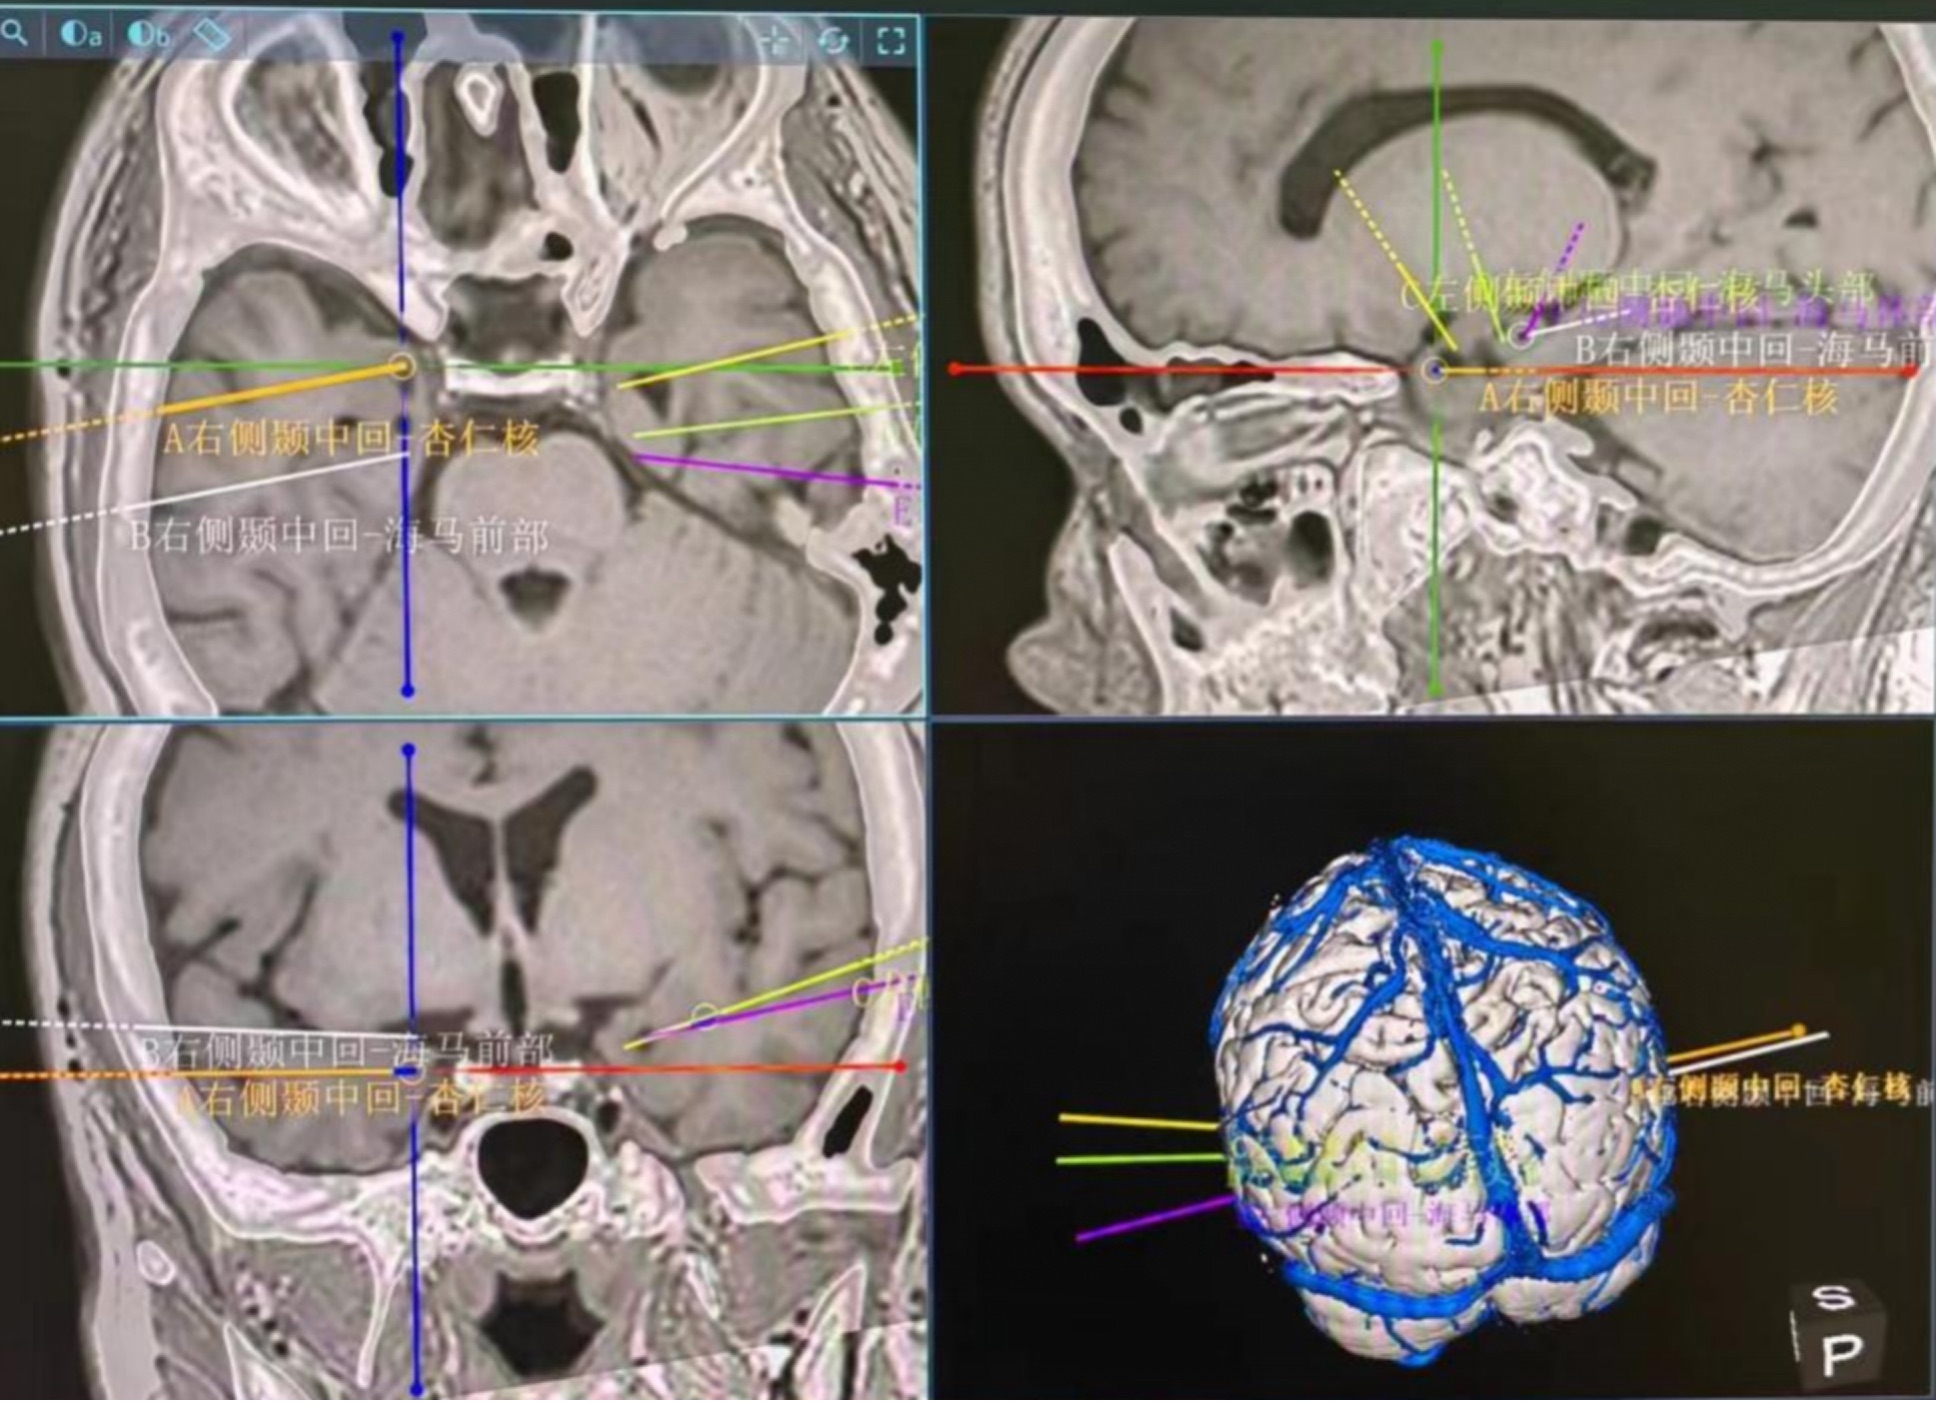

于是,黄绳跃主任医师团队为患者实施立体定向SEEG手术。在手术机器人的精确引导下,成功将脑深部电极植入患者双侧杏仁核、海马等部位。术后视频脑电图监测证实了患者癫痫发作起源于左侧颞叶杏仁核,也为后续手术切除致痫灶奠定了坚实基础。在明确致痫灶后,黄绳跃主任医师团队为患者实施了左侧标准前颞叶切除术。

▲机器人辅助下的脑深部电极植入计划